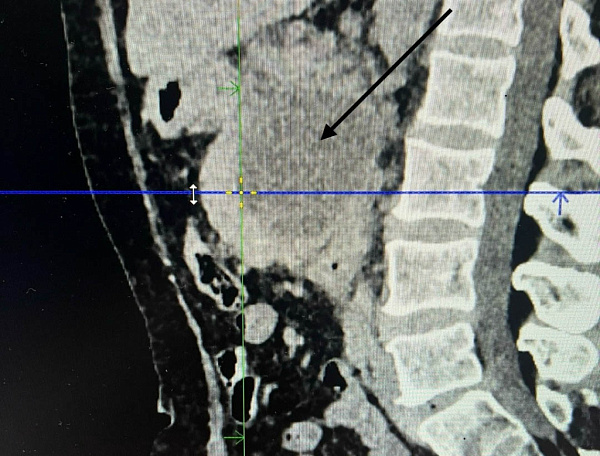

Для проведения операции пациентку транспортировали в больницу скорой медицинской помощи в Улан-Удэ. Врач-хирург медучреждения выполнил уникальную операцию, сделав дренирование кисты под УЗИ наведением.

– Сложность этой операции заключается в том, что поджелудочная железа располагается под желудком в сальниковой сумке, рядом располагаются толстый и тонкий кишечник. Нужно найти безопасное пространство, а это не так просто, чтобы не повредить желудок, толстый и тонкий кишечник, пройти иглой в полость кисты поджелудочной железы и по игле провести дренаж до 5 мм в диаметре, – пояснил Адриан Тармаев.